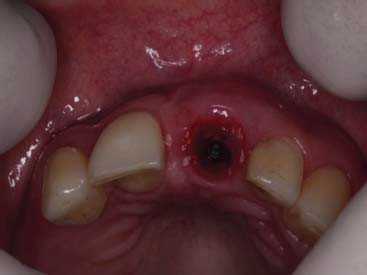

A paciente ERL, gênero feminino, 28 anos, procurou atendimento relatando dor na região anterior superior, com histórico de trauma prévio durante a mastigação. Na avaliação da paciente, o dente 21, aonde havia uma coroa cerâmica instalada com núcleo metálico, apresentava uma fratura obliqua, gengiva edemaciada, com sinais clínicos de infecção na parede vestibular do alvéolo (figura 1 e figura 2). O plano de tratamento incluiu a indicação de exodontia do dente 21, seguida de um implante imediato (Straumann® Bone Level SLActive) associado a um cicatrizador personalizado para manter a caracterização do contorno gengival do elemento.